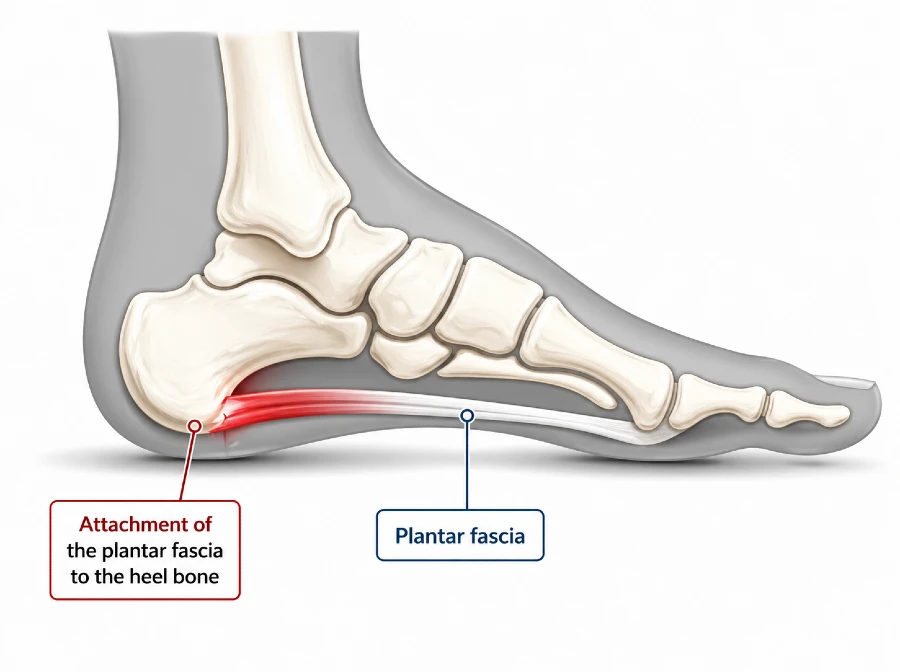

Plantar fasciitis is the leading cause of heel pain in adults and one of the most frequent musculoskeletal conditions of the foot encountered in clinical practice. It is a condition characterized by degenerative irritation of the plantar fascia at its attachment to the heel bone, most often as a result of repetitive mechanical overload.

The plantar fascia is a strong, fibrous band of connective tissue located on the underside of the foot. It is anatomically designed to withstand high mechanical loads during standing, walking, and running.

It originates from the inferior aspect of the calcaneus (heel bone) and extends forward toward the forefoot, where it fans out and attaches to the bases of the toes through multiple fibrous bands.

The central portion of the plantar fascia is the thickest and strongest, playing the key role in maintaining the longitudinal arch of the foot. The medial and lateral portions are thinner and follow the natural contour of the foot.